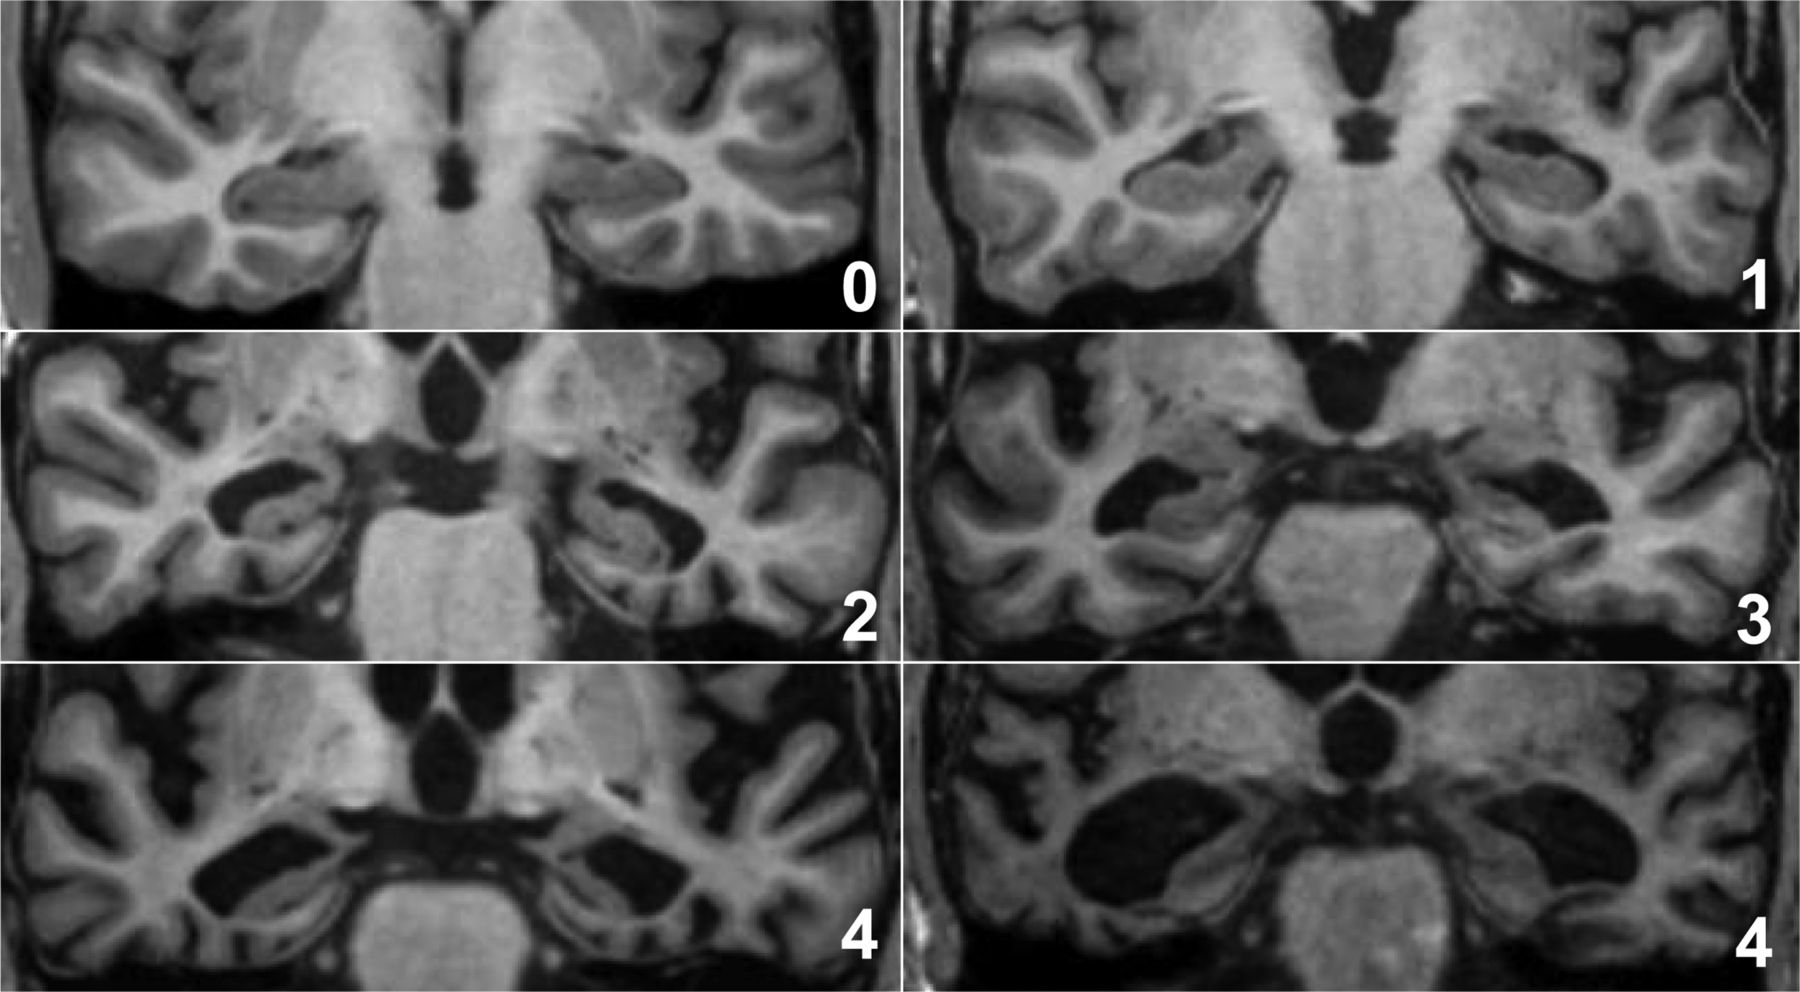

Fazekas grades. Koedam мрт шкала. Koedam на мрт. Шкала Фазекас мрт. Koedam Grade MRI.

Fazekas grades. Koedam мрт шкала. Koedam на мрт. Шкала Фазекас мрт. Koedam Grade MRI.